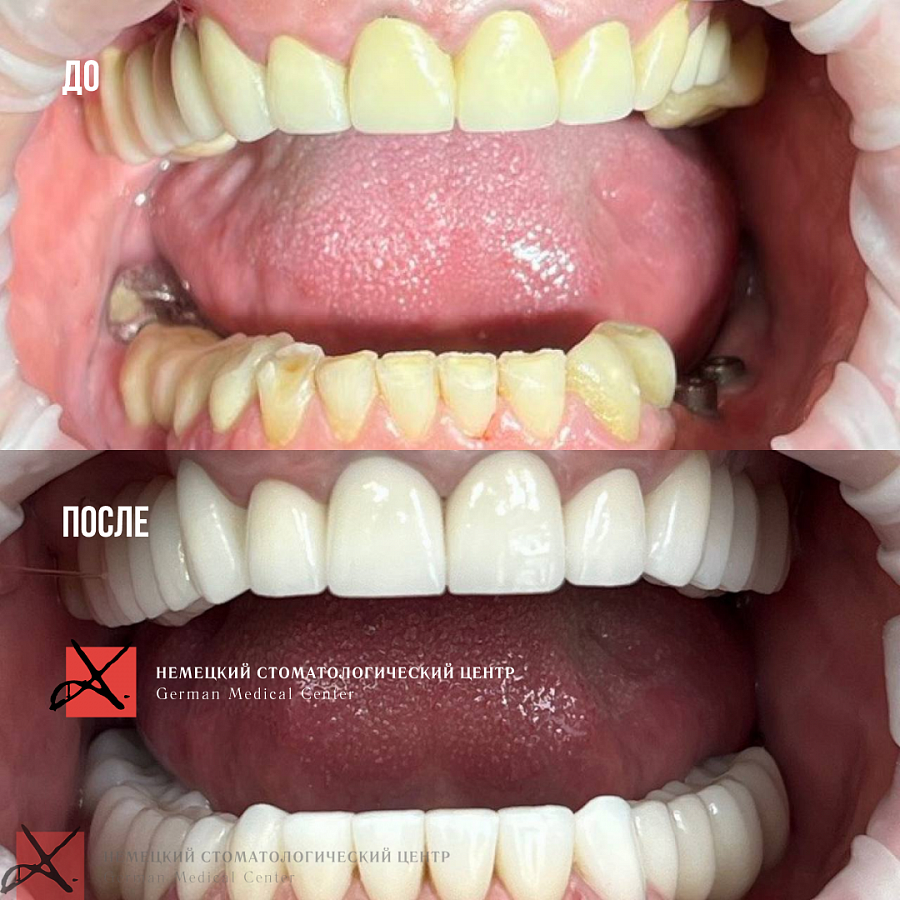

Эстетические проблемы, неровные зубы жёлтого цвета, искривление губ при улыбке. В добавок ко всему у пациента было очень старое протезирование, под которым было совершенно непонятно, в каком состоянии находятся зубы.

Во-первых, поменяли цвет зубов и выровняли контур. Получилась очень красивая форма зубного ряда. Как следствие, выровнялись губы, улыбка приобрела симметричную форму. Восстановили высоту нижней трети лица, пациент начал хорошо дышать. Теперь зубы смотрятся очень эстетично, ничего не беспокоит, пациент очень доволен.

Во-первых, поменяли цвет зубов и выровняли контур. Получилась очень красивая форма зубного ряда. Как следствие, выровнялись губы, улыбка приобрела симметричную форму. Восстановили высоту нижней трети лица, пациент начал хорошо дышать. Теперь зубы смотрятся очень эстетично, ничего не беспокоит, пациент очень доволен.